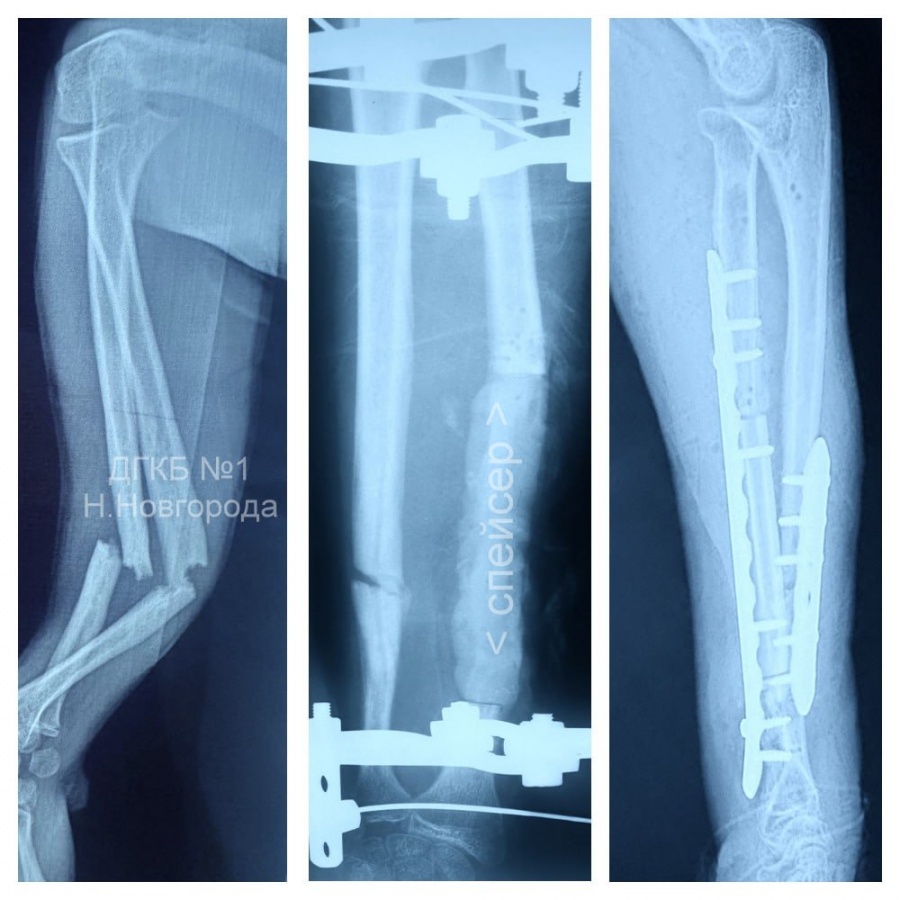

В рамках первого этапа лечения специалисты удалили гнойный очаг, а также девять сантиметров уже омертвевшей кости. Вместо этого участка был установлен антимикробный спейсер с химиопрепаратами. Кроме того, врачи заново поставили аппарат Илизарова.

Уже на втором этапе подростку провели костную пластику, заменив дефект трансплантатом из его же малой берцовой кости. Локтевую кость, которая так и не смогла правильно срастись, распилили, а кости предплечья зафиксировали пластинами.